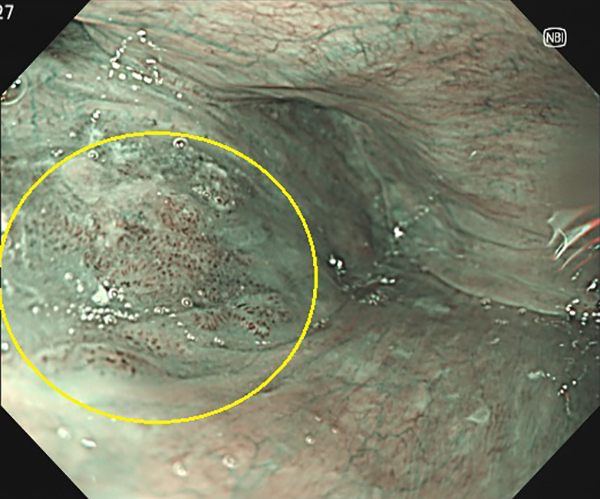

②下咽頭癌-2(経口拡大内視鏡)

右下咽頭(右喉の奥)にNBI画像処理で茶色に見えるわずかな隆起を認めます。

内視鏡的粘膜切除術で治癒、径10×9mmの扁平上皮癌と診断されました。